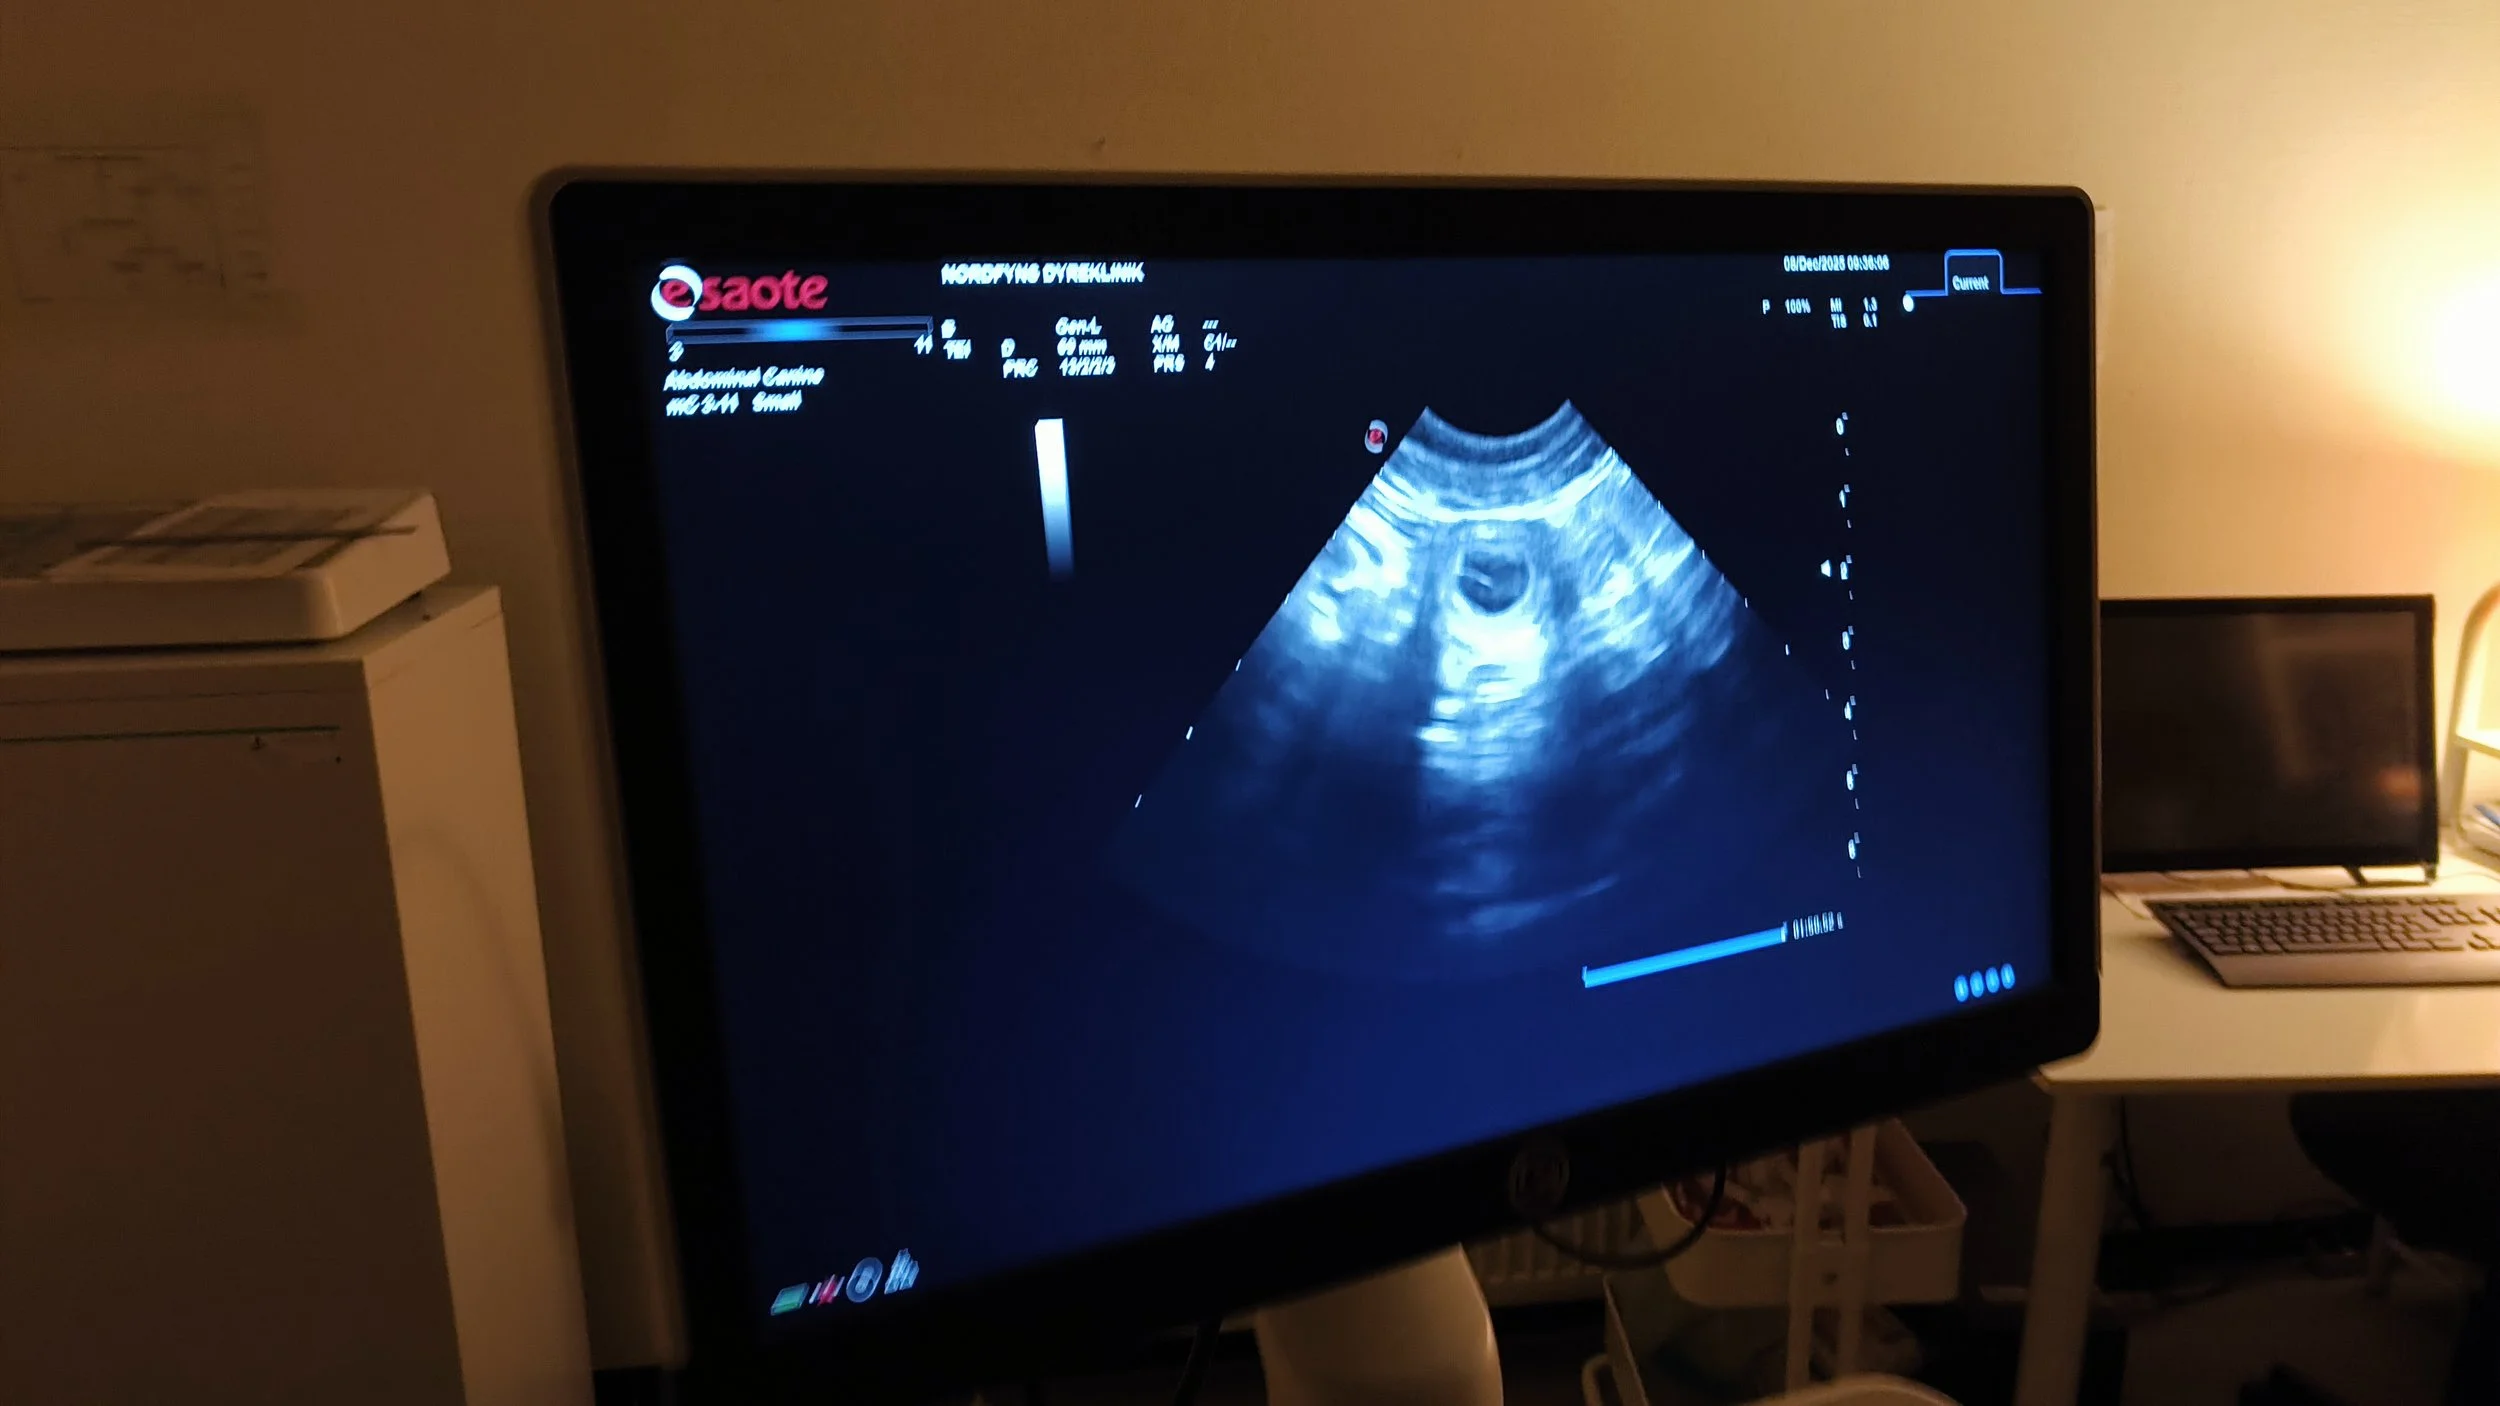

Scanning af Juno viste fine små bobler, og det har været dejligt at følge hendes udvikling her i december. Stadig glad og oplagt, men i takt med den forøgede mave mærkes det tydeligt, at hun bliver hurtigere træt. Og appetitten fejler ingenting!